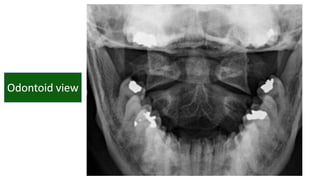

• #22 Flooe of post cranial fossa Angle of mand Ant post arch of atlas Dens of axis Harris ring is a ring like structure resulting from proj of lat masses of c2 on its body Laminae of c2 Retropharyngeal retrotracheal

• #33 Basion dense interval <9.5mm